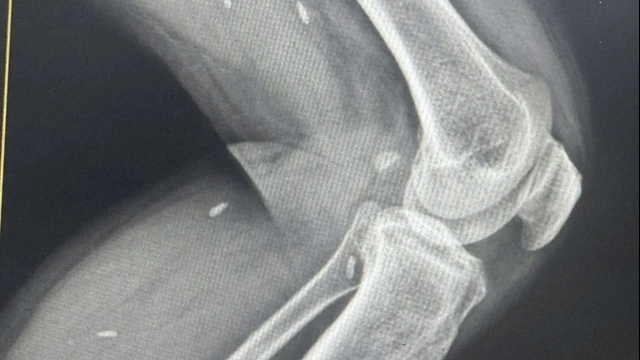

Bệnh nhân được cấp cứu tại bệnh viện tuyến tỉnh, chụp cắt lớp vi tính sọ não không tiêm thuốc cản quang và dựng mạch máu não.

Tuy nhiên, trong những giờ đầu, trên phim cắt lớp vi tính sọ não không tiêm thuốc cản quang chưa phát hiện tổn thương nhu mô não, không phát hiện các tổn thương thường gặp sau chấn thương sọ não như tụ máu ngoài màng cứng, dưới màng cứng hay dập não máu tụ trong nhu mô não.

Bệnh nhân được chụp ngay cắt lớp vi tính sọ não có tiêm thuốc cản quang và dựng mạch hệ thống mạch máu não, kết quả cho thấy hình ảnh tắc hoàn toàn động mạch cảnh trong bên phải và tổn thương nhồi máu não diện rộng bán cầu não bên phải.

Với mức độ tổn thương thiếu máu não rộng bệnh nhân không còn chỉ định các biện pháp can thiệp tái thông mạch não nhằm phục hồi nhu mô não thiếu máu.